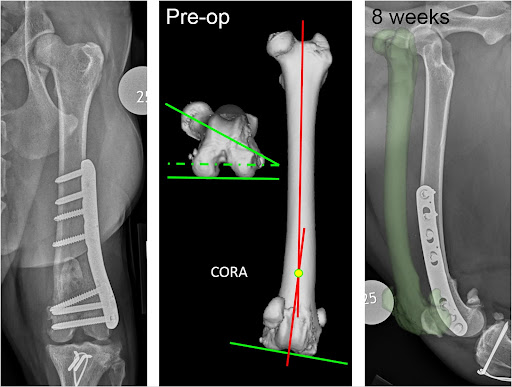

- Femoral osteotomy

- In severely bow-legged dogs, the thigh bone (femur) has to be surgically cut and remodelled to create a normal straight leg (Figure 6).

Figure 6: Distal femoral osteotomy (Perry and Dejardin 2021).